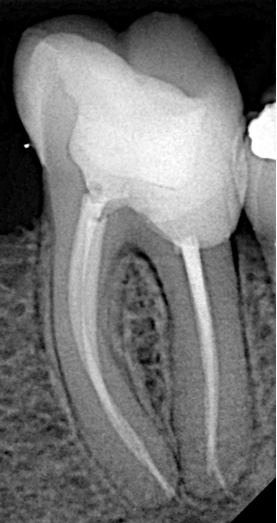

Step 5: Obturation and Restoration

Obturation was completed using the hydraulic condensation technique, which leverages sealer hydraulics for excellent adaptation and a true 3D seal, particularly beneficial in irregular or curved canals. A final composite restoration sealed the access cavity, restoring both function and coronal integrity.

Outcome and Takeaways

This case demonstrates that even advanced endodontic scenarios — involving zirconia crown removal, large periapical pathology, and severe root curvature — can be predictably managed non-surgically with careful planning, proper armamentarium, and meticulous technique. The tooth was successfully preserved, avoiding extraction and more invasive treatment options.